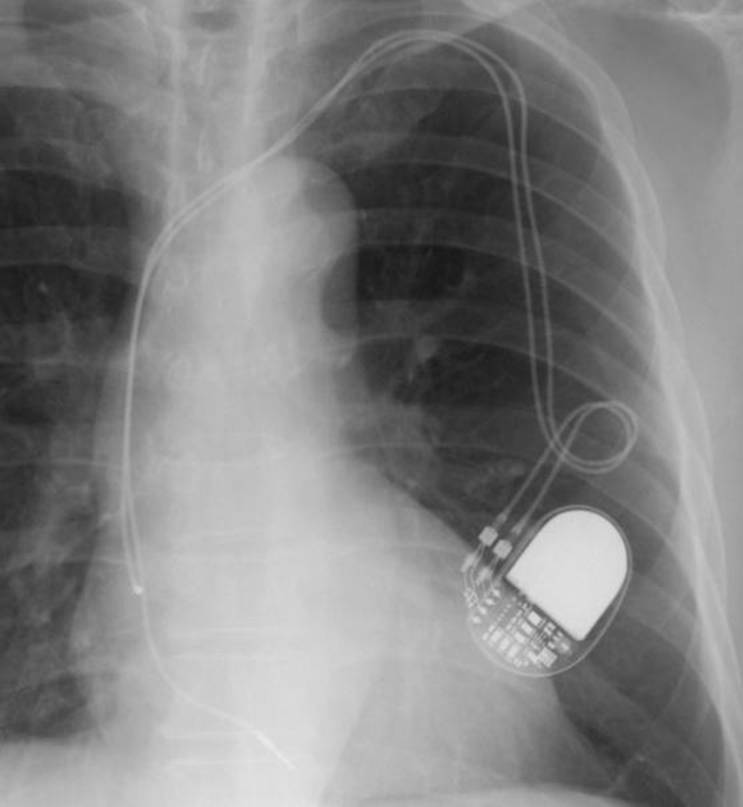

1.病名、症状:人工ペースメーカー感染

2.手術名とその内容:手術日2012/01/24 ペースメーカー除去、体外ペーシング、新規再移植時(ペースメーカー植込み術)、鎖骨の下に4-5cmの皮膚を切開し、5cm程度のポケットを作成します。その中に、心臓内に挿入したリード線1~2本と電池(ジェネレータ)を植え込みます。

新規のPMは、メーカーを変える。MRI(magnetic resonance imaging=磁気共鳴映像法)対応でドイツ製とのこと(国内では駄目)。サイズは従来のものより大きいというので、皮膚に負担が掛かると、感染の原因となるのではと。感染しないことが、大切ですからと、先生。

第5回目となる手術は、リード(2本)の除去、ジェネレーター(PM)の除去、入院前に腫脹した箇所の切除となる。

PMはどうやら取り出せた。次にリードであるが、スクリューイン(先端がキルクをあける時のツール状)されている。S先生が1,2,3,・・・と数えながらそれぞれを回し始める。モニターでは分解性能のせいか、抜け切れたのか、不明のようだ。其の時の痛みは全く無い。リードの抜けた部分を切る。静脈に挿入する手前の各リードにストッパー状のもの(リードを固定するためにかしめる物で其の上を糸で縛る)が取り付けてあるようだ。これを見つけないと残余のリードを取り出せない。困難に打ち当たる。剣ヶ峰だ。

駈け付けた別の先生が、“これは(あと)1時間以上かかるぞ”と。どうやら少し離れた場所の椅子に座り、引き継いだ先生と外科のT先生の問いに指示を出している。辛うじて1本は見つかった。が、もう一本に窮している。もっと先かな、と切り開き抉る。ウッ、痛い、う~ん。T先生、手前じゃないかと少し戻って切除。あった! 2本ともスムーズに引き出せた。2008年05月20日以来3年8ヵ月か。

2012012402PM

ペースメーカーは、BIOTRONIK社製、エヴィア(Evia DR-T電池寿命14年)に替わった。ホームモニターリングをし、ドイツにあるセンターへPMのロギングデータを夜中に毎日送る。MRIにも耐えるということだが、日本では承認されていない。

2012020201PM(植込み中のため、体外式ペーシング利リードもある)

2012021001PM

2012020202PM

2012020203PM